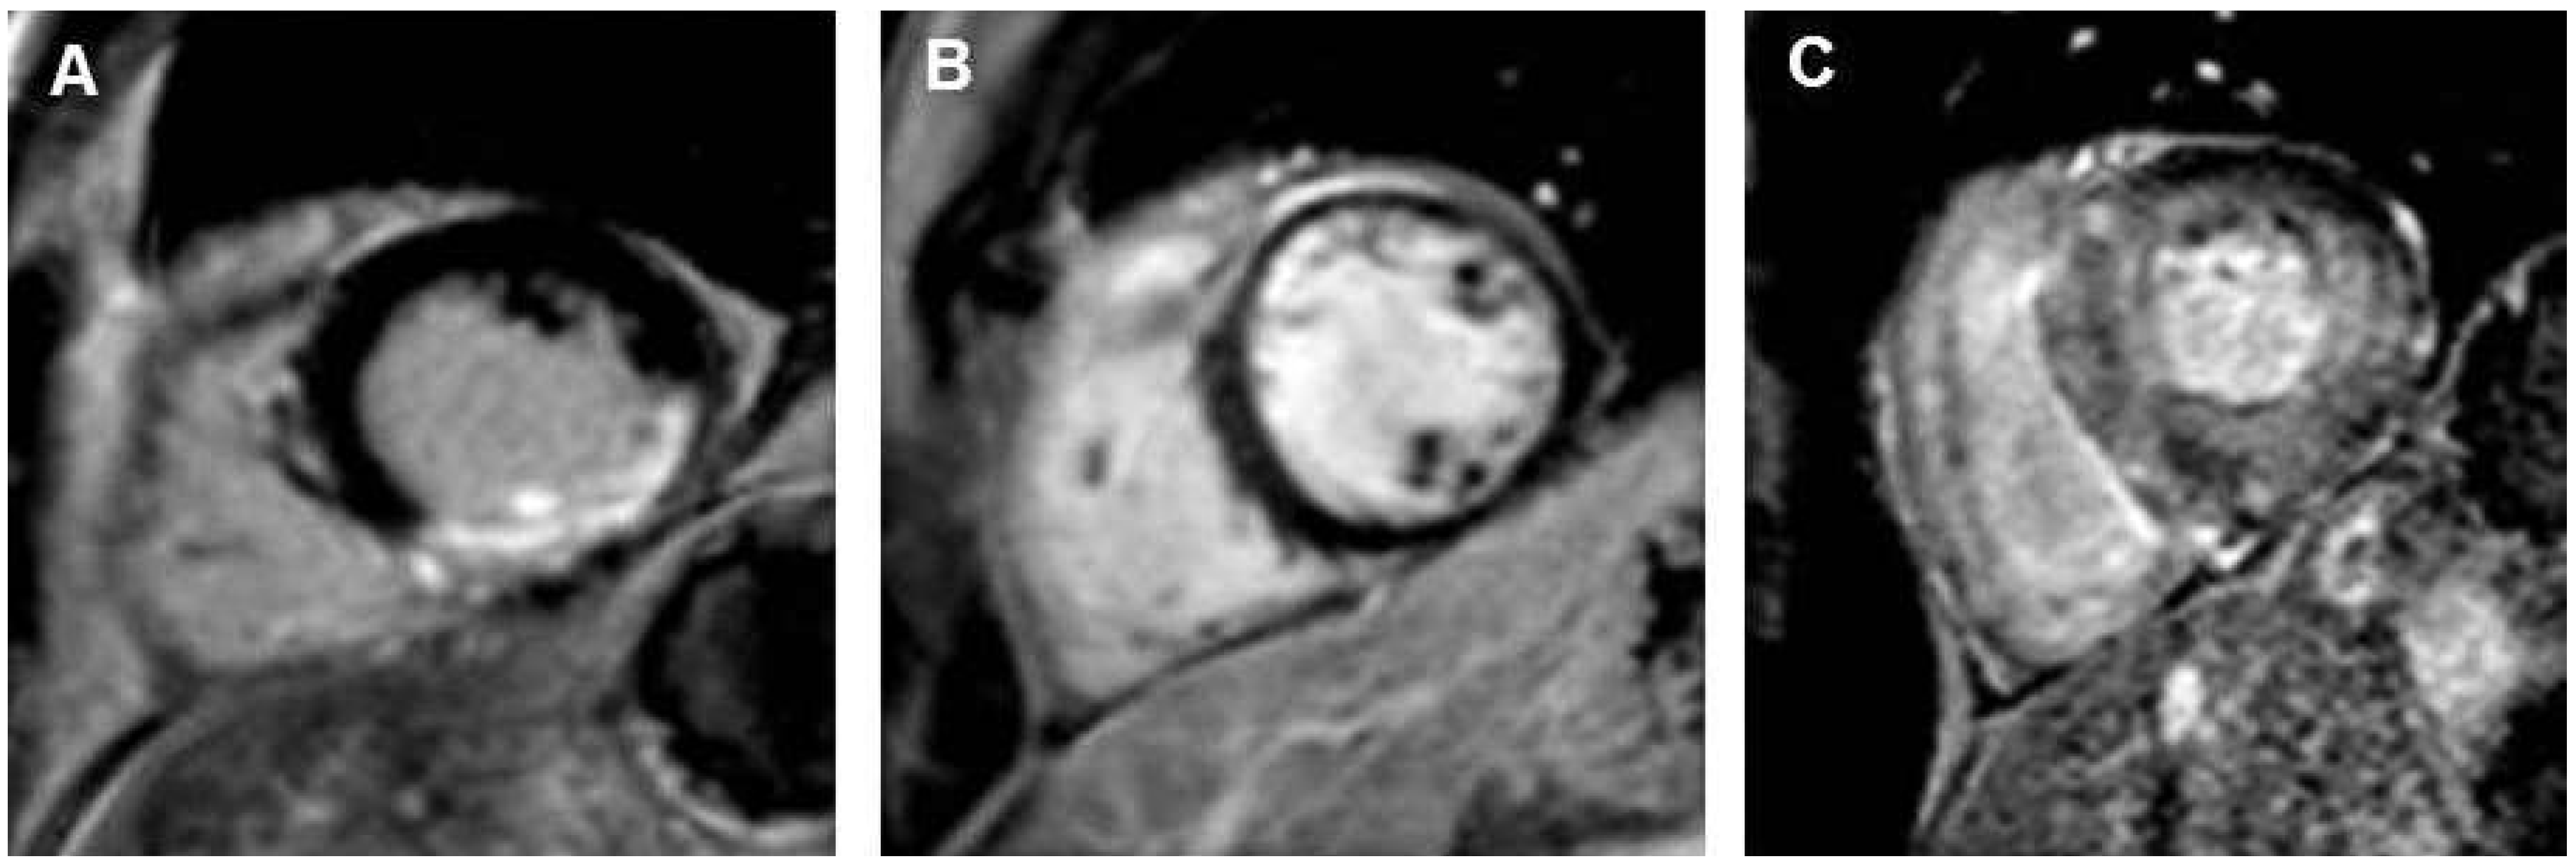

Myokardiale Perfusionsuntersuchung

Die Herz-MRI-Perfusionsuntersuchung beruht auf der Darstellung der Passage eines gadoliniumhaltigen Kontrastmittels während der Hyperämiereaktion, die durch einen pharmakologischen Vasodilatator erzielt wird. Da Gadolinium ein positives Kontrastmittel ist (hell in T1-gewichteten Aufnahmen), stellt sich normal perfundiertes Myokard während der pharmakologisch induzierten Hyperämie hell in T1-gewichteten Aufnahmen dar. Myokardsegmente, die unter pharmakologischer Hyperämie nicht oder verzögert perfundiert werden, kommen dunkel zur Darstellung (Figure 2A). Um die Anzahl falsch-positiver Befunde aufgrund von Arte fakten zu minimieren, kann eine Ruheperfusion angeschlossen werden (Figure 2B). Die Kontrastmitteldosis beträgt zwischen 0,05 und 0,1 mmol/kg Körpergewicht. Üblicherweise kommt als Vasodilatator Adenosin zum Einsatz, das intravenös über mindestens 3 Minuten verabreicht wird. Adenosin hat eine kurze Halbwertszeit (ca. 12 Sekunden) und ist eine sichere Substanz für die klinische Verwendung [16]. Als wichtigste Kontraindikationen sind allergisches Asthma bronchiale, schwere obstruktive Lungenerkrankungen und höhergradige AV-Blockierungen zu nennen, als weitere Kontraindikationen sind Sinusknotendysfunktionen und schwere Hypo- oder Hypertonie aufzuführen. Seltene Nebenwirkungen sind Bronchospasmus und eine transiente AV-Knotenblockierung. Mittlerweile gibt es alternative Substanzen, wie den selektiven A2a-spezifischen Adenosinrezeptoragonisten Regadenoson, der in Europa verfügbar ist und ein geringeres Neben wirkungsspektrum aufweist [17,18]. Die überwiegende Anzahl klinischer Studien wurde bei Feldstärken von 1,5 Tesla durchgeführt, so dass die grösste Evidenz hierauf beruht. Neuere vergleichende Studien zur Diagnostik relevanter Koronarstenosen zeigen eine Überlegenheit der Perfusionsuntersuchung bei einer Feldstärke von 3 Tesla [19,20]. Die Aufnahmesequenz sollte T1-gewichtet und EKG-getriggert sein [21]. Die Perfusionsaufnahme dauert ca. 10 Sekunden und wird unter Atemanhalt durchgeführt, um Bewegungsartefakte möglichst gering zu halten [22]. In der Regel werden drei Schichten (basal, midventrikulär und apikal) des linken Ventrikels in axialer Orientierung aufgenommen. Neuere Verfahren erlauben mittlerweile auch die dreidimensionale (3D-)Erfassung myokardialer Perfusion und somit auch die Bestimmung des prozentualen Anteils ischämischen Myokards [15,23–25]. In der klinischen Routine wird die Perfusion visuell analysiert. Bei speziellen Fragestellungen oder wissenschaftlichen Untersuchungen kann eine quantitative, automatisierte Auswertung durchgeführt werden.

Figure 2. (A,B) zeigen die typischen 3 Kurzachsenorientierungen des linken Ventrikels, die während einer Perfusionsuntersuchung aufgenommen werden. (A) zeigt eine belastungsinduzierte Perfusionsstörung in der lateralen linksventrikulären Wand. (B) Unter Ruhebedingungen liegt keine Perfusionsstörung vor. C zeigt viables Myokard in den Late-gadolinium-enhancement-Aufnahmen auch in den Myokardsegmenten, die unter Belastung eine Perfusionsstörung aufweisen. Es liegt eine belastungsinduzierte Isch ämie vor.